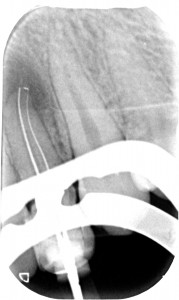

Con l’ausilio della Cone Beam sono riuscito a identificare che il dente aveva due canali e una radice molto palatoversa: per accedere a questi canali, separati tra loro dall’istmo di smalto invaginato, potevo fare una cavità perpendicolare al dente a livello vestibolare e una palatina.

Non ho smontato subito il composito perché mi serviva a riconoscere i reperi che mi ero cercato sulla tac.

La prima cavità, fuori dagli schemi, ho preferito farla senza diga per capire meglio l’inclinazione. Guarda che spettacolo la cavità di accesso!

Una volta trovato il canale con l’accesso più difficile e sapendo che un secondo canale decorreva parallelo a questo dal lato palatino il resto è stato relativamente semplice.